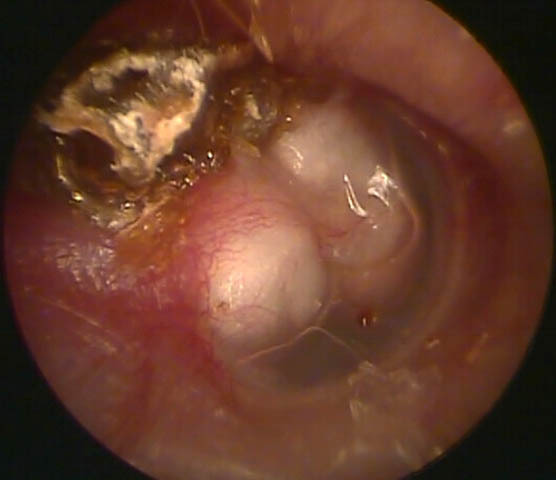

Question 1 : Vous examinez les tympans. Voici ce que vous constatez. Que pouvez-vous dire de ce tympan ?

Le manche du marteau penche vers l’avant, et le triangle lumineux est dans le cadrant antéro-inférieur

La myringite bulleuse correspond à une inflammation du tympan avec une phlyctène dans le tympan. Ici les bulles sont rétro-tympaniques

Lorsqu’il y a une perforation, il y a un trou dans le tympan par lequel le fond de caisse est visible. Les berges de la perforation sont généralement bien repérables.

Il y a en effet une poche de rétraction au niveau de l’attique.

Il n’y a aucun signe local d’inflammation (rouge, aucun antécédent d’otorrhée, etc.)

Rappel sur le tympan normal : le tympan est quasiment transparent avec le marteau bien visible et bien moulé. Le triangle lumineux (reflet de la lumière) est visible dans le quadrant antéro-inférieur. Le tympan n’est pas bombant mais tendu (pars tensa), de façon radiaire à partir de l’extrémité du manche du marteau. La pars flaccida est la partie du tympan immédiatement au-dessus de l’apophyse externe du marteau.

La difficulté est parfois de distinguer une poche de rétraction d’une perforation. Ce n’est pas toujours facile et peut nécessiter un diagnostic spécialisé. Dans la plupart des cas, une perforation est bien limitée et les berges bien visibles. Dans le cas d’une poche de rétraction, le fond de caisse peut être moulé par la rétraction mais on voit généralement des reflets du tympan.

Vous constatez donc une poche de rétraction de la pars flaccida. Vous décidez de l’exploration avec un tympanogramme. Vous retrouvez le tympanogramme suivant.